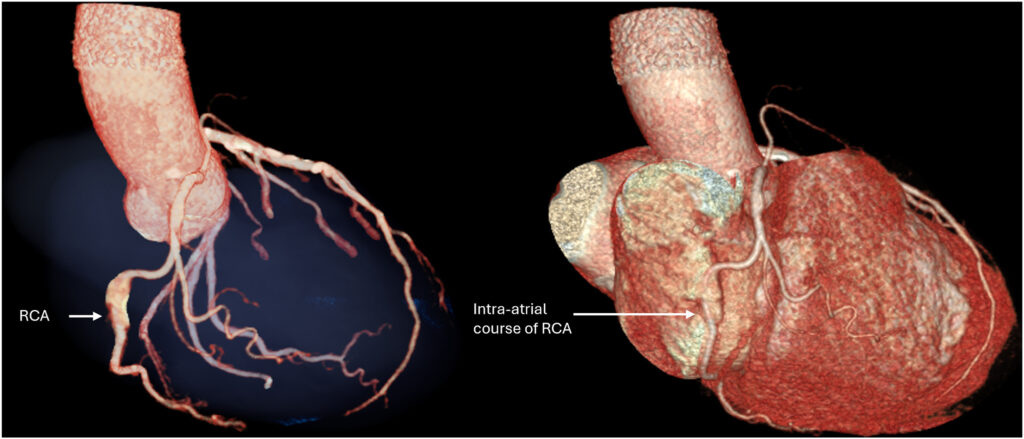

O exame mostrou origens normais tanto da CD quanto da coronária esquerda, com presença de lesão aterosclerótica com estenose moderada na DA, bem como confirmou a suspeita de trajeto anômalo da CD, com o seguimento médio apresentando curso intra-atrial transversal de 3.5 cm.

A reconstrução 3D ilustrou, de forma muito didática, o trajeto intracavitário da coronária direita.